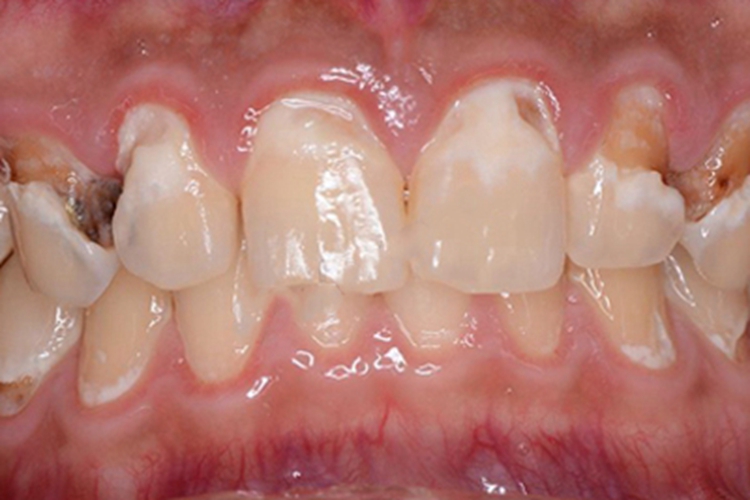

酸蚀症可见到受累部位的牙齿表面有形状不规则的白斑,大部分靠近牙根部,部分牙齿已出现缺损、凹陷,露出牙骨质,凹陷处呈黄色及褐色,患者可出现牙齿敏感症状,受刺激后易有牙龈出血表现。